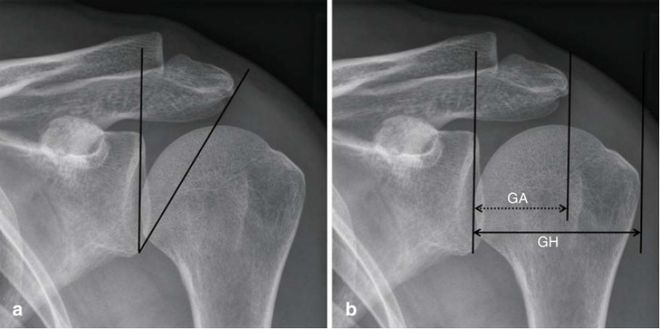

临界肩角(CSA):从关节盂平面和肩峰外侧缘之间的关节盂下极测量的角度,较大的CSA是肩袖病变的危险因素,如果CSA 超过35°,则发生撞击发生肩袖撕裂的风险更高。

肩肱指数(Al):这是从关节盂表面到肩峰外侧端的距离GA和从关节盂表面到肱骨头外端的距离GH的商:根据定义,AI= GA/GH,高AI提示肩峰明显外侧延伸,这与肩袖撕裂风险增加显著相关。